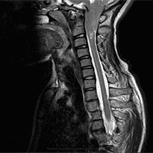

Il metodo Filum System® è originale, in primo luogo perché basato su di una ricerca scientifica approvata cum laude dalla commissione di tesi di dottorato di Royo Salvador, nella quale si dimostra l’esistenza di una nuova Malattia, quella Del Filum, causa di altre patologie associate- quali l’Arnold-Chiari I, la Siringomielia e la Scoliosi idiopatiche e altre- e finora sconosciuta.

In secondo luogo, il trattamento che propone consiste in una tecnica chirurgica mini-invasiva, risultato di una ricerca in proprio, che riduce i rischi di un intervento classico di sezione del filum terminale, tanto per la tecnica quanto per l’anestesia, che è locale.

Se il trattamento prescelto è maggiore ed invasivo- per la Sindrome d’Arnold Chiari I la decompressione suboccipitale e per la Siringomielia la siringostomia-, si è soliti raccomandarlo particolarmente ai casi sintomatici, dato che applicarlo può provocare più morbilità e mortalità che il normale progresso della patologia. (https://institutchiaribcn.com/it/patologie/sindrome-arnold-chiari/ https://institutchiaribcn.com/it/patologie/siringomielia/)

Se, invece, l’intervento prescelto è di Sezione del Filum Terminale per la Malattia del Filum con la tecnica del Filum System®, i suoi svantaggi si riducono a possibili scarse complicazioni della ferita chirurgica- come infezione o deiscenza- come in qualsiasi intervento chirurgico, senza deficit neurologico, né morbilità, né mortalità.